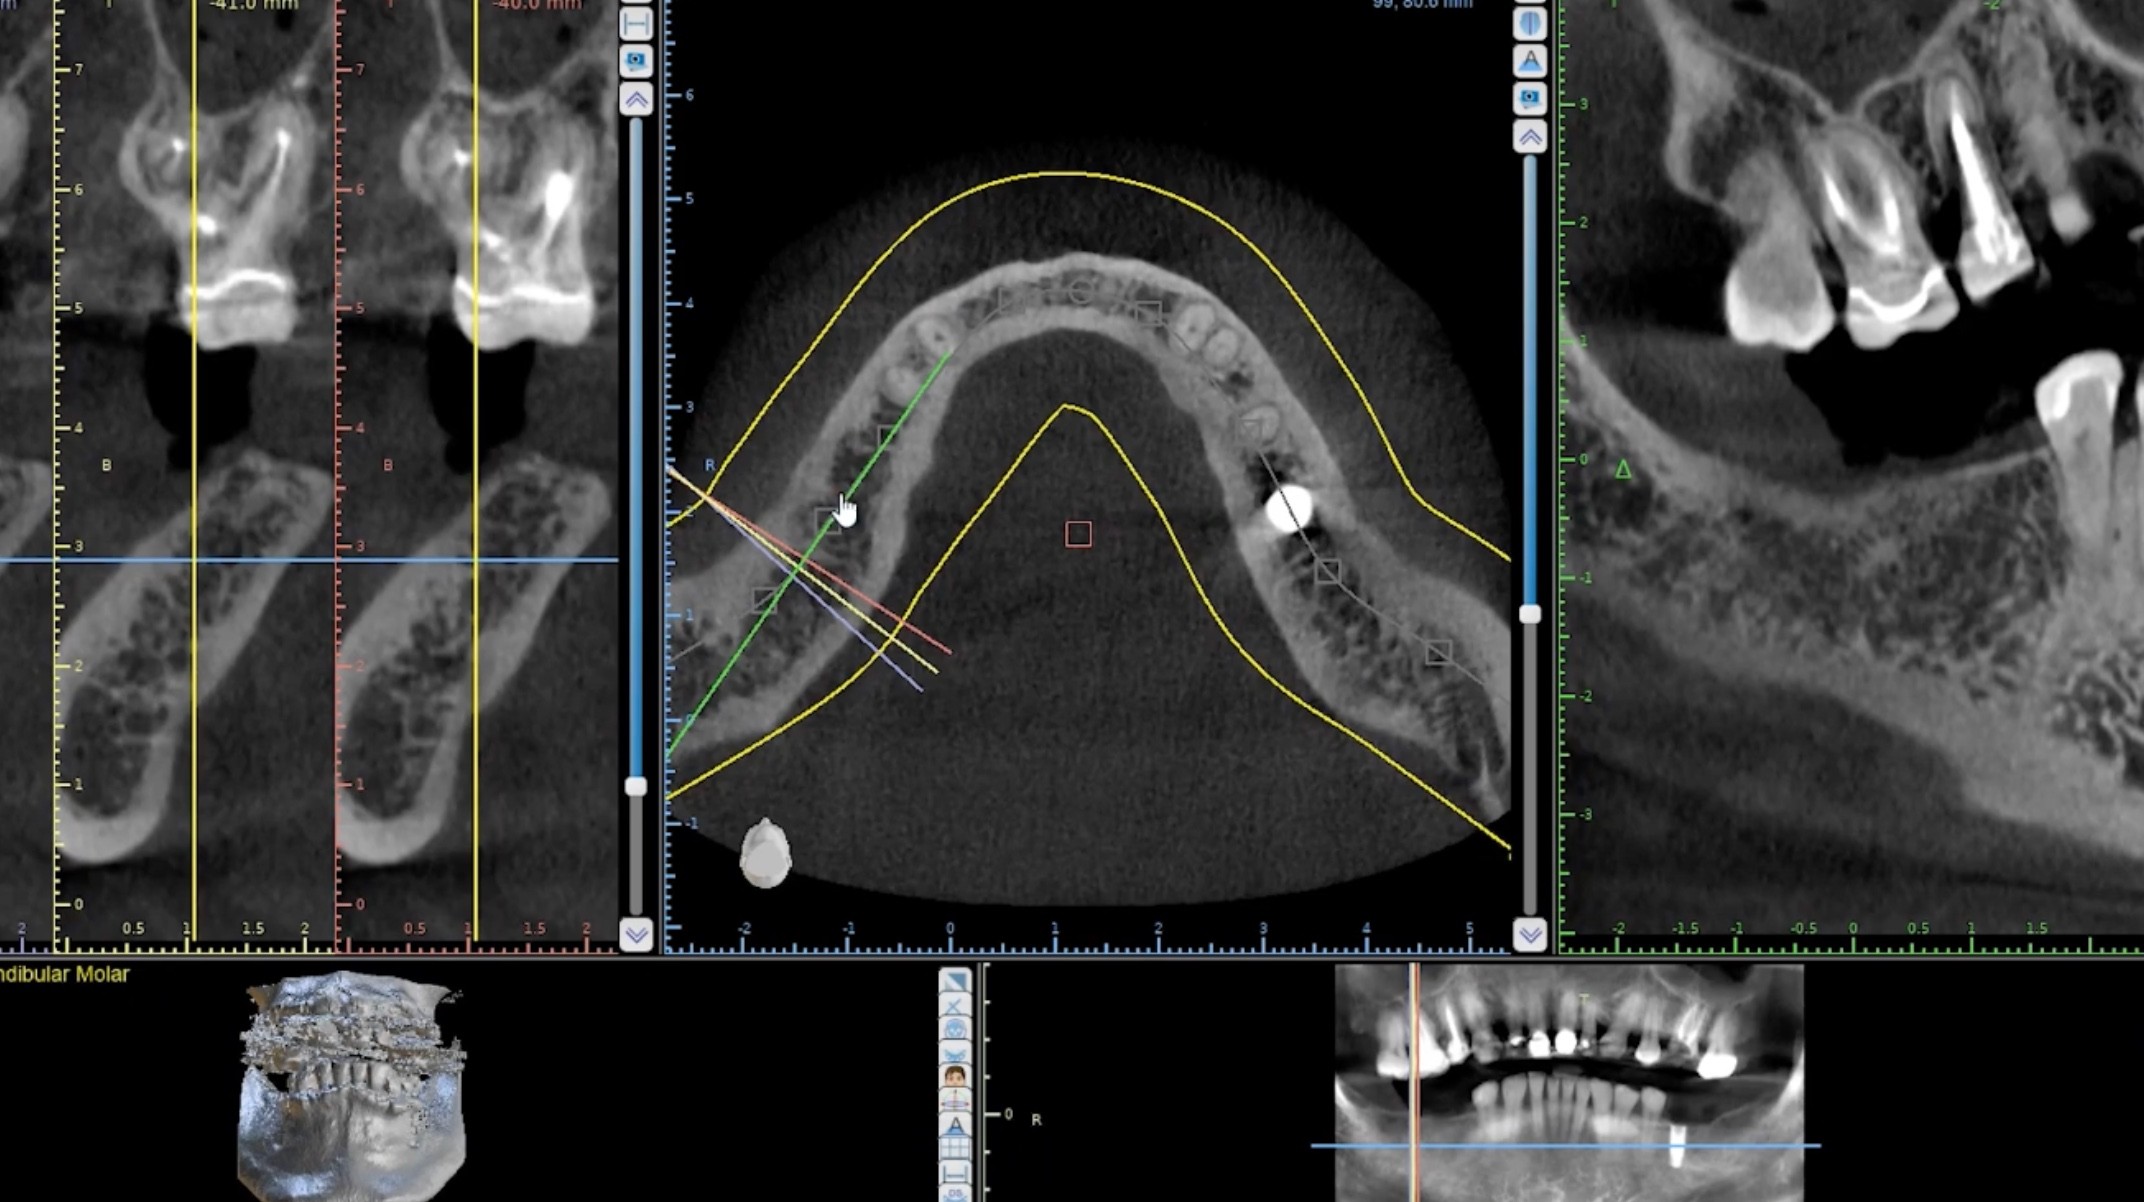

Radiological Interpretation Course

In this course we cover how to evaluate radiographs for the purposes of implant surgery. We cover panoramic radiographs to Cone Beam CTs and provide sample patient data for your analytical exercises.